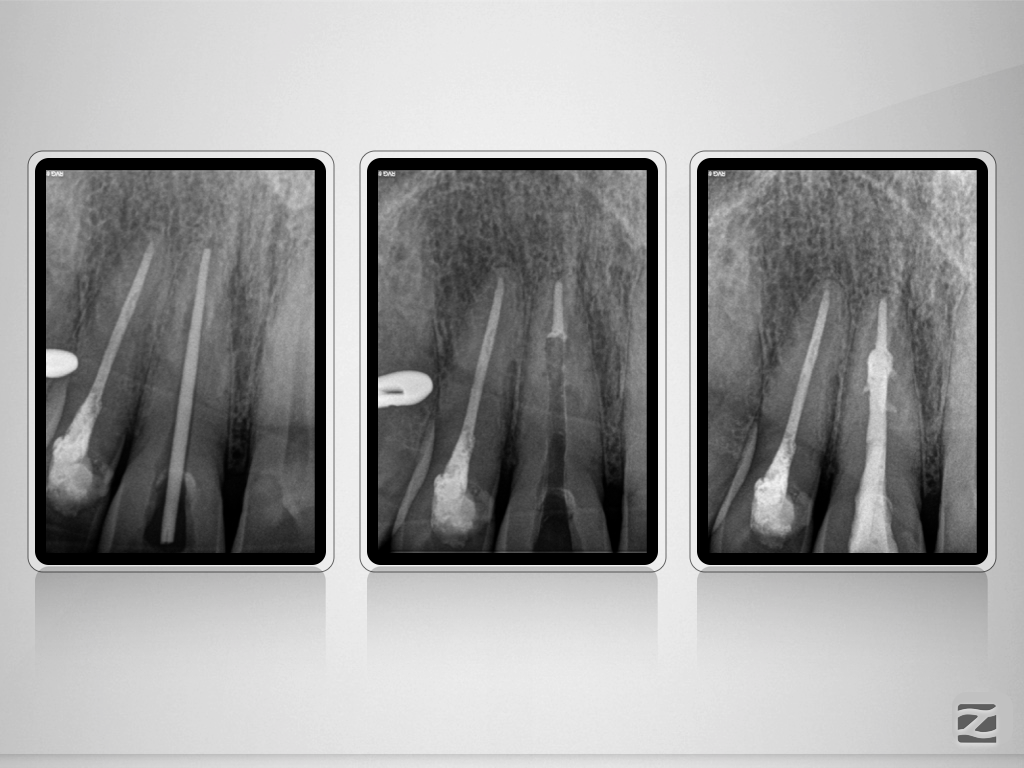

Unverhofft und nicht oft.